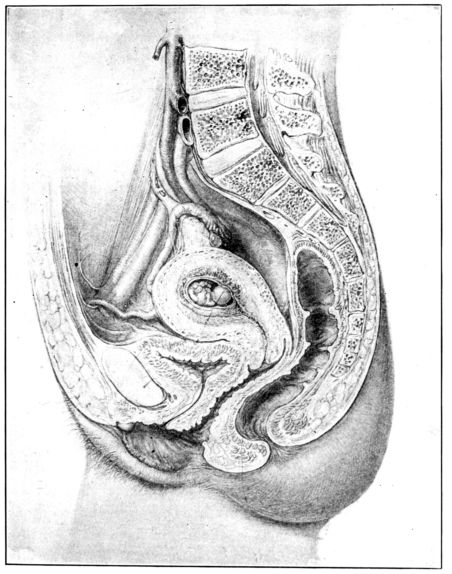

| 12. | Sagittal section of female generative tract | 35 |

Fig. 12.—Sagittal section of female generative tract. Drawn by Max Brodel. (Used by permission of A. J. Nystrom & Co., Chicago.)

The vagina is an elastic, muscular sheath or tube, about four inches long, lying behind the bladder and urethra and in front of the rectum. It leads interiorly up and backward from the vulva to the cervix, which it encases for about half an inch. The space between the outer surface of the cervix that extends into the vagina, and the surrounding vaginal walls, is called the fornix. 36For convenience of description, this is divided into four sections or fornices: the anterior, posterior and lateral fornices.

Between the posterior fornix and the rectum a fold of the peritoneum drops down and forms a blind pouch known as Douglas’ cul-de-sac. At this point the delicate peritoneum is separated from the vagina by only a thin, easily punctured, muscular wall. This is a fact of grave surgical significance, for unless instruments and nozzles introduced into the vagina are very gently and skillfully directed, they may easily pierce this thin partition. Septic material may thus gain entrance to the peritoneal cavity and peritonitis result.

This oblong, muscular body, the uterus, is suspended obliquely in the centre of the pelvic cavity by means of ligaments. In its normal position the entire organ is slightly curved forward, or ante-flexed, the fundus being directed upward and forward and the cervix pointing down and back. This position is affected by a distended bladder or rectum, and also by postural changes in the body as a whole. The cervix protrudes into the anterior wall of the vagina for about one-half inch and almost at right angles, since the vagina slopes down and forward to the outlet.